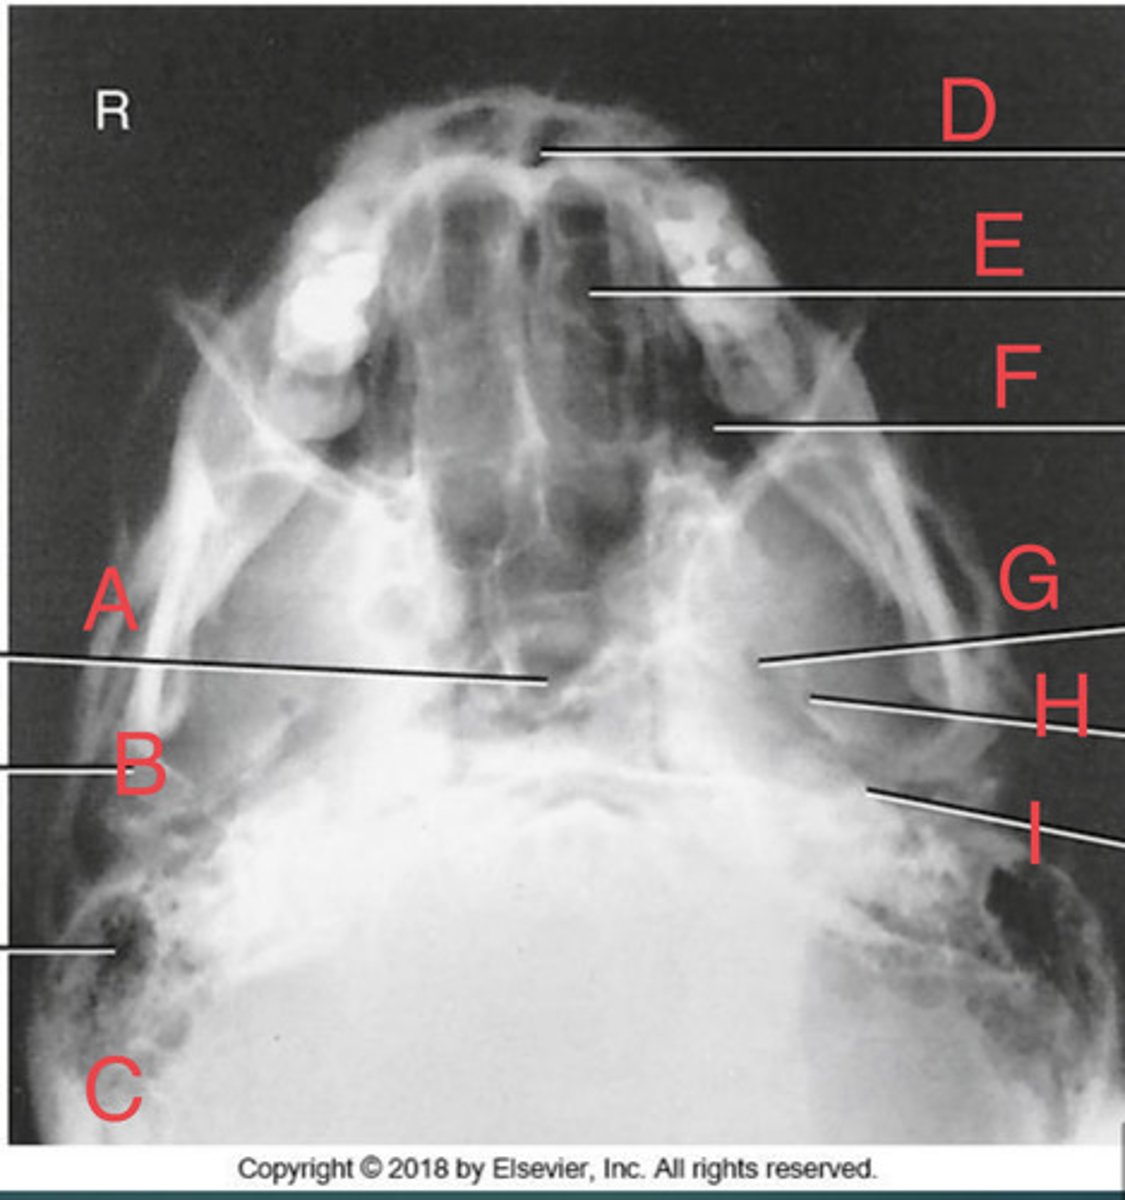

SMV sinuses

What position?

Sphenoid sinus of sphenoid bone

A.

R mandibular condyle of mandible

B.

R Mastoid air cells of temporal bone

C.

Nasal fossa

D.

L. Ethmoid sinus of ethmoid bone

E.

L maxillary sinus of maxilla

F.

L foramen ovale of sphenoid bone

G.

foramen spinosum of sphenoid bone

H.